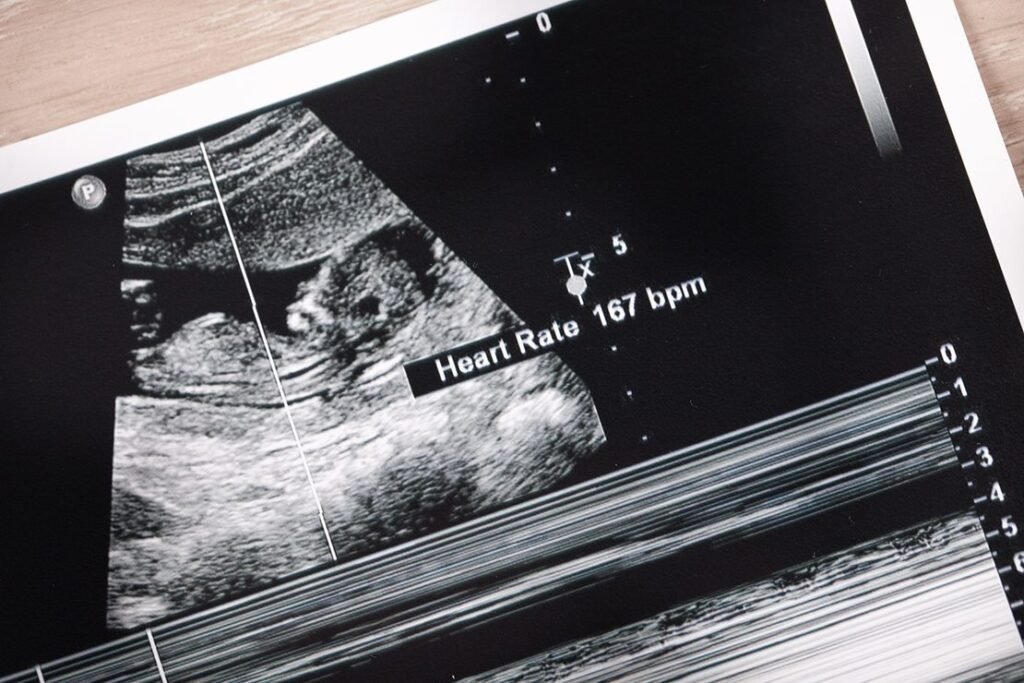

One of the most common questions expectant parents ask after hearing their baby’s heartbeat is, “Does the fetal heart rate tell me if it’s a boy or a girl?” When you see a heart rate of 158 beats per minute (BPM) on your ultrasound report, it’s easy to wonder whether that number means you’re carrying a daughter or a son. The idea that a baby’s heart rate can predict gender has been passed down for generations.

A healthy fetal heart rate typically ranges between 110 and 160 beats per minute throughout most of pregnancy. Early in the first trimester, the fetal heartbeat starts lower — around 90 to 110 BPM — and gradually increases as the baby grows. By around week 9 or 10, it usually peaks between 170 and 180 BPM before settling into a stable rhythm in the normal range.

So, a fetal heart rate of 158 BPM is perfectly normal — neither too high nor too low.

A fetal heart rate of 158 beats per minute sits near the higher end of the normal range. This is typical, especially during early or mid-pregnancy. It simply means your baby’s heart is developing and functioning well.

Doctors use fetal heart rate readings mainly to monitor fetal well-being, checking for proper rhythm, accelerations, and overall variability. As long as the heart rate stays between about 110 and 160 BPM, there’s no need for concern or assumption about gender.